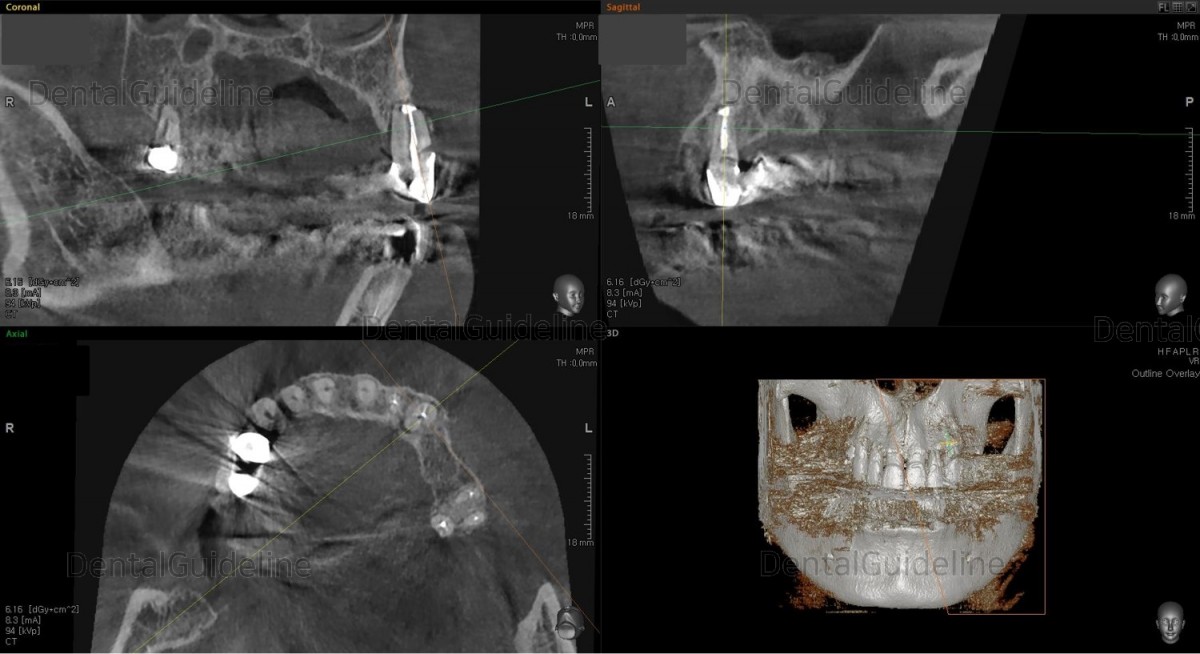

CBCT

CBCT. 2.5 years of the apicoectomy.